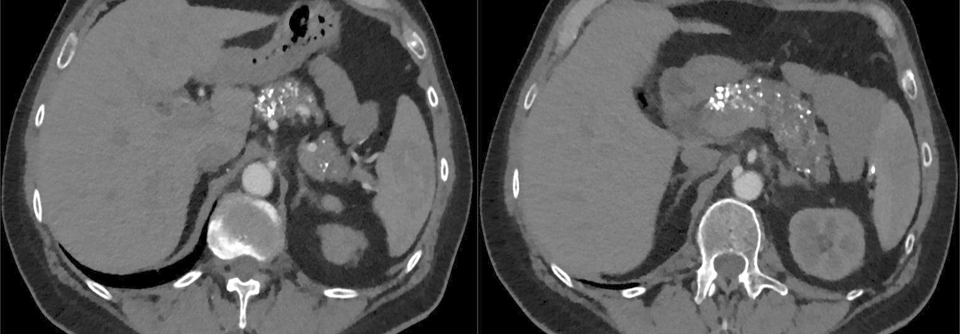

Bei einer 46-jährigen Frau wird eine akute Pankreatitis diagnostiziert. Die Patientin hat einen BMI von 35 und erhält wegen ihres erst kürzlich festgestellten Typ-2-Diabetes Metformin. Aufgrund von Wechseljahresbeschwerden wurde ihr zudem eine Hormonersatztherapie verschrieben, zur kardiovaskulären Primärprävention nimmt sie Statine. Zum Zeitpunkt der Pankreatitisdiagnose sind der Blutzucker mit 306 mg/dl und vor…